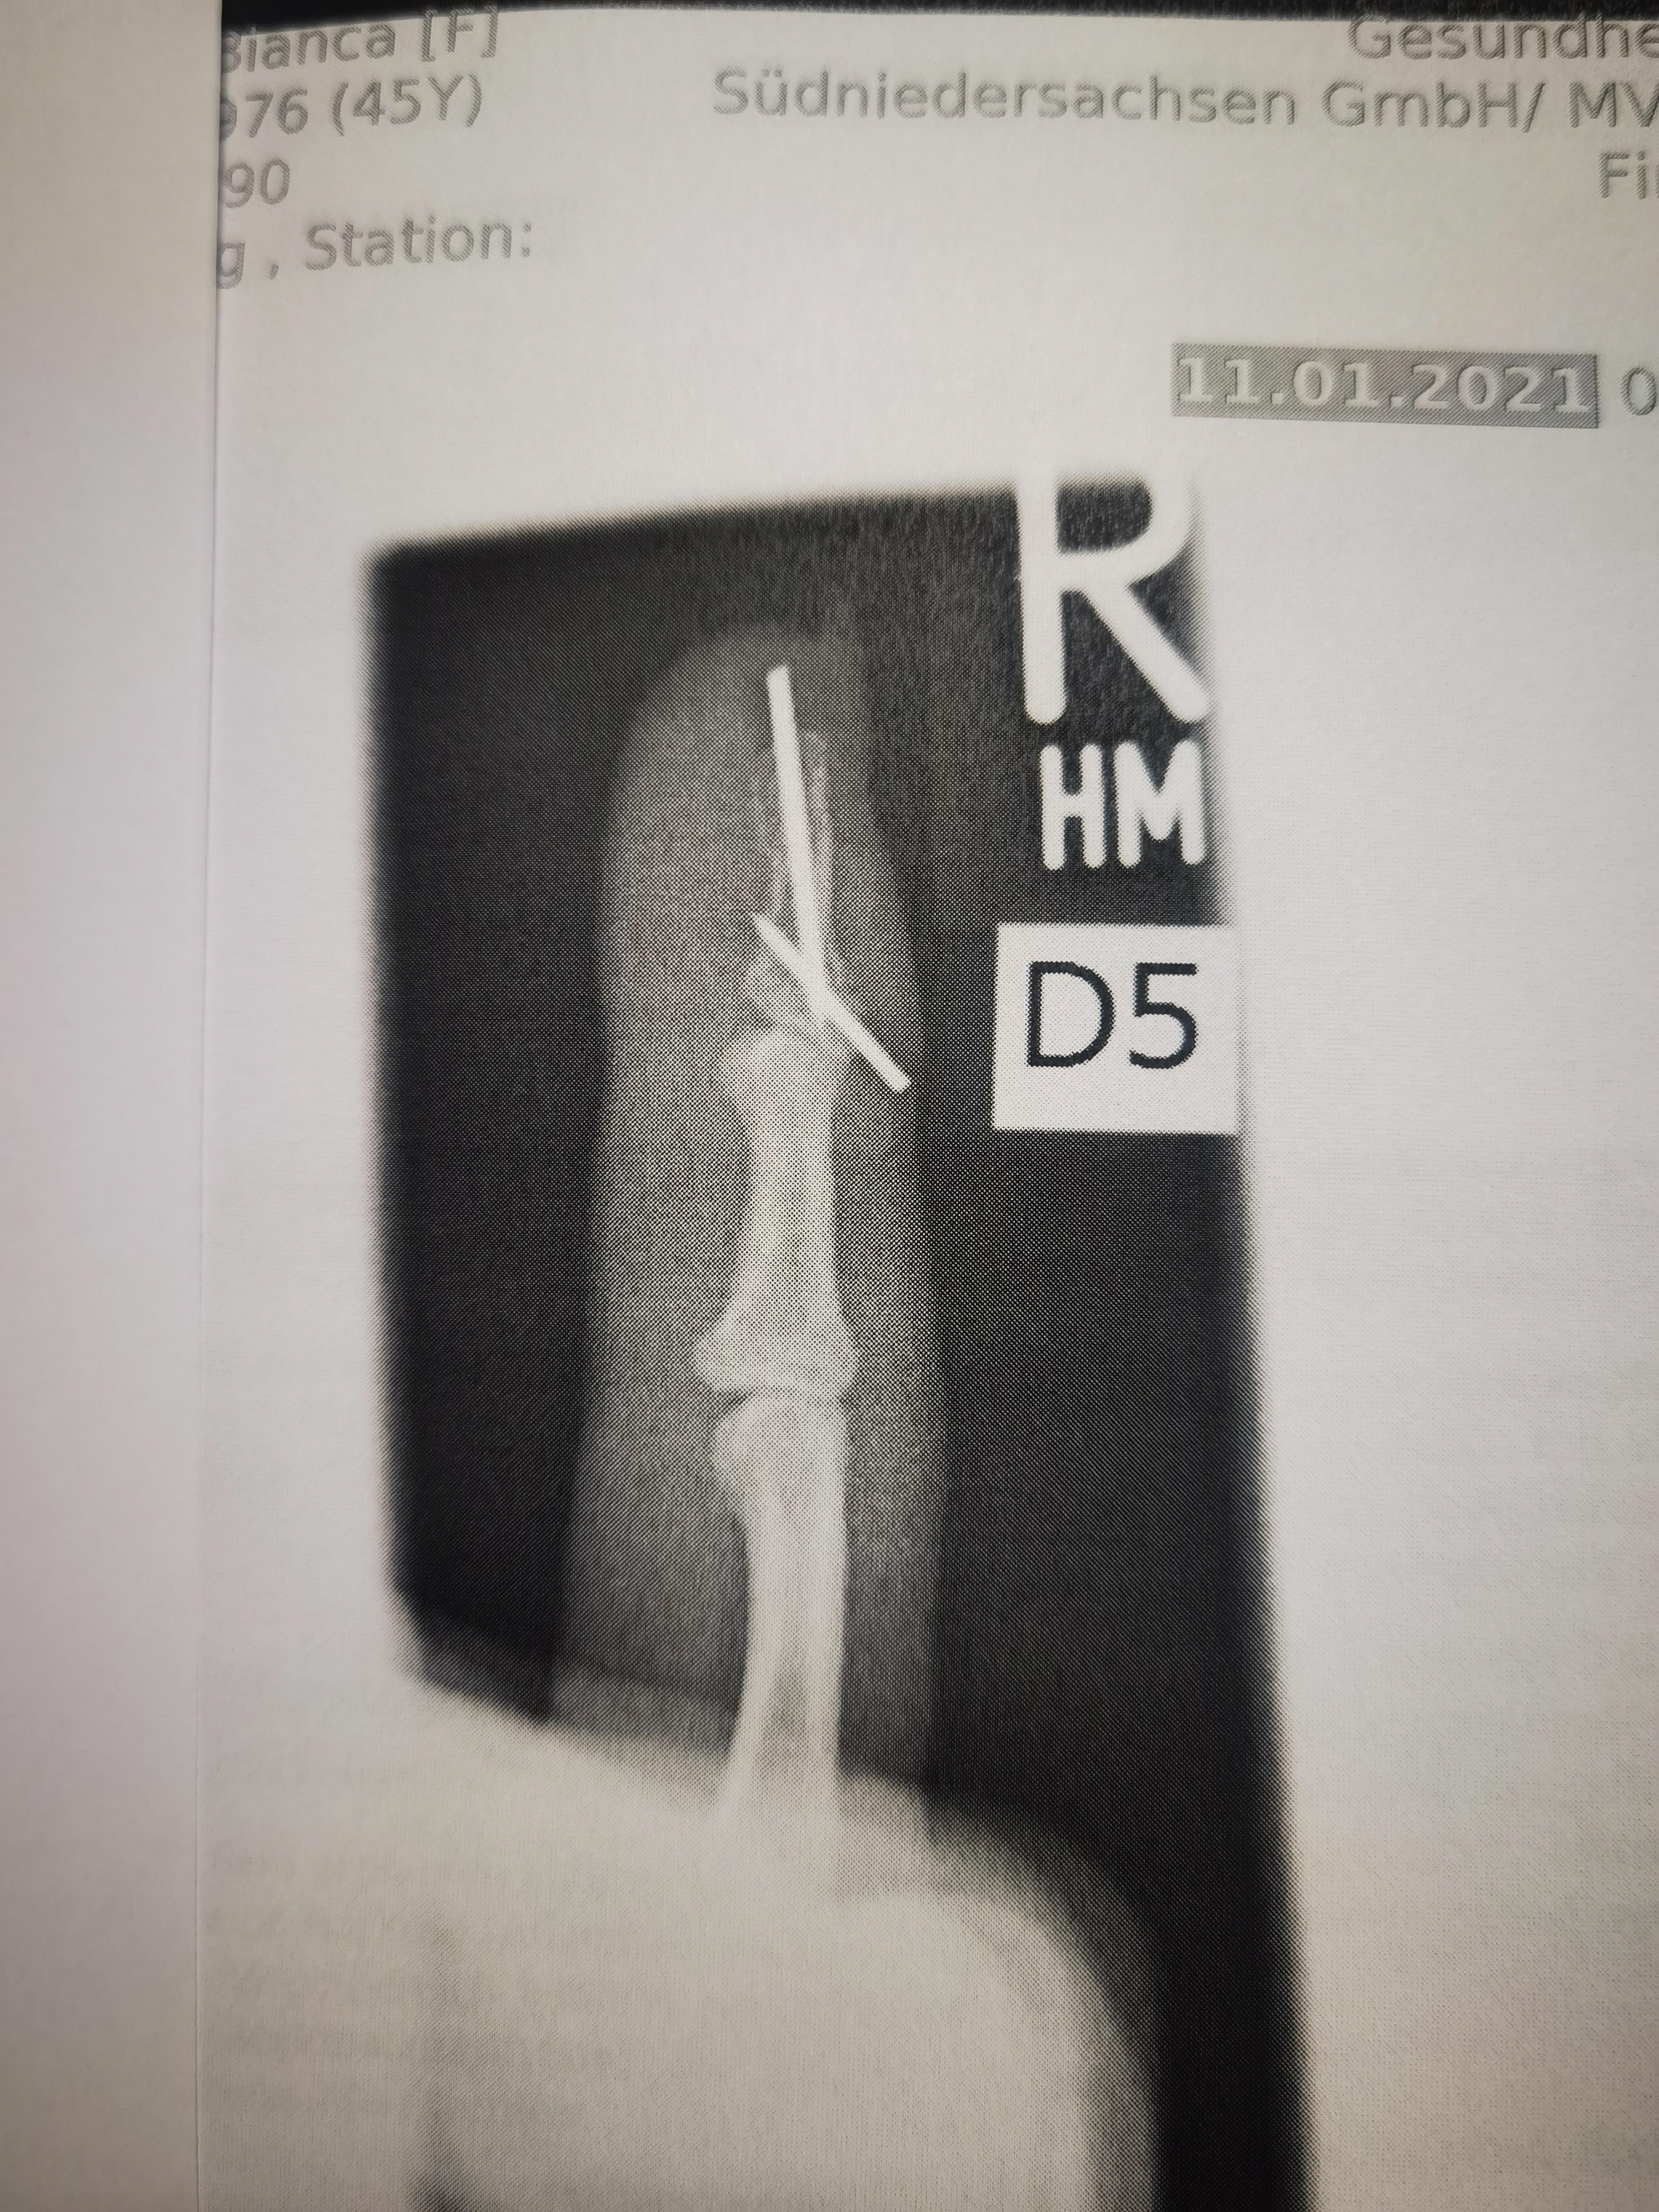

Im Falle eines Knochenbruches werden die meisten Drähte nach 6-8 Wochen entfernt. Kirschnerdraht von Zeh entfernen K-wire removal from my toe. Ein Kirschner-Draht ist ein aus Edelstahl oder Titan bestehender Draht von 05-3 mm Dicke der zur Osteosynthese verwendet wird.

Die werden sehr unproblematisch entfernt. Kirschner draht entfernen finger Kirschner-Draht - ist ein Draht der eine Bohrerspitze an einem Ende die durch weiches Gewebe in den Knochen gebohrt wird um direkt zur Stabilisierung der Knochen während es heilt hat. Legen Sie die betroffene Extremität oder Anhängsel auf eine flache stabile Oberfläche.

Dies geschieht nach einigen Wochen während Ihres Kontrolltermins in unserer Sprechstunde. Bei meiner Hand-OP haben sie mir auch eine Plexus-Anästhesie angeboten. Siehe Bilder unten Jetzt ist meine Frage. Wenn Brüche der oberen Extremität bei Kindern versorgt werden müssen zählt die Osteosynthese mit Kirschner-Drähten zu den Standardverfahren um Knochen zu stabilisieren. Dabei ist es möglich die Knochenfragmente minimal-invasiv punktuell und ohne Kompressionseffekt zu fixieren. Kirschnerdraht von Zeh entfernen K-wire removal from my toe - YouTube. Entfernen Sie die Schiene. Ziehen Sie den Zugbolzen mit dem 25-mm-Sechskantschraubendreher wieder fest. Eigentlich kann er gut mit Schmerzen umgehen.